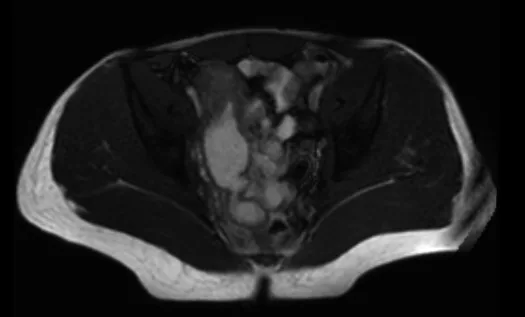

L’entéro-IRM est l’examen de référence pour l’évaluation et le suivi de l’évolution de l’atteinte iléale de la maladie de Crohn (Fig. 1).

L’entéro-IRM a l’avantage par rapport à l’entéroscanner d’être un examen non irradiant pour des patients souvent jeunes qui vont nécessiter des examens répétés. L’examen est habituellement pratiqué 50-60 min après l’ingestion de 1 000 mL de Mannitol et l’administration d’un traitement limitant le péristaltisme intestinal. L’utilisation d’une sonde nasogastrique ou duodénale est actuellement abandonnée afin d’améliorer la tolérance de l’examen. L’entéro-IRM permet d’évaluer la topographie des lésions [8], l’activité inflammatoire de la maladie [9, 10], le caractère plus ou moins sténosant et le retentissement d’amont de la sténose [8], la longueur de l’atteinte [11], l’existence de lésions associées à distance et de complications [8, 12] en cas de maladie perforante. Enfin, l’entéro-IRM peut également évaluer l’efficacité des traitements avec une précision proche de l’examen endoscopique [13]. En ce qui concerne le choix de la stratégie thérapeutique, plusieurs études ont tenté de déterminer s’il existait des facteurs prédictifs en imagerie de succès ou d’échec du traitement médical et notamment des anti-TNF. Une étude récente portant sur 112 malades ayant une maladie de Crohn a montré que l’évaluation en entéro-IRM permettait de prédire le recours à une chirurgie. En effet dans cette étude, le caractère sténosant de l’atteinte en IRM et l’existence d’une fistule interne étaient associées à une augmentation du risque de recours à une intervention chirurgicale. Ces résultats semblent confirmés par l’étude CREOLE effectuée par le GETAID [14] dont un des objectifs était de déterminer les facteurs prédictifs de réponse aux anti-TNF en cas de maladie de Crohn iléale sténosante. Dans cette étude, l’existence d’une rétrodilatation de plus de 29 mm, l’absence de prise de contraste intense et tardive sur les séquences pondérées en T1 et l’existence d’une fistule sur l’entéro-IRM étaient associées à une moins bonne efficacité des anti-TNF.